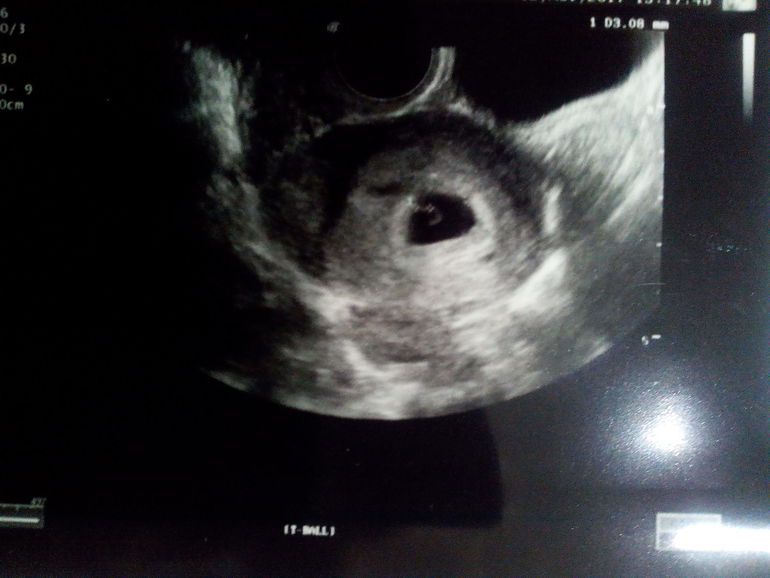

Первое УЗИ в 6 недель

В итоге сегодня сходила на УЗИ в Инвитро.

Брач успокоил... Б в матке, видно пока что только ПЯ, желточный мешочек и эмбрион. Ну как эмбрион... Точка, размером 3мм.

Но я рада, главное мой страх ушёл. Беременность маточная. Через 1,5 недельки сказал можно прийти ещё, и что приятно прием будет уже со скидкой 50% ))

Мне до сих пор не верится, что эта точечка на экране мой малыш)))

Эмбриональный срок почему то не сказал. Может рано ещё и не понятно... Написал 5-6 недель.